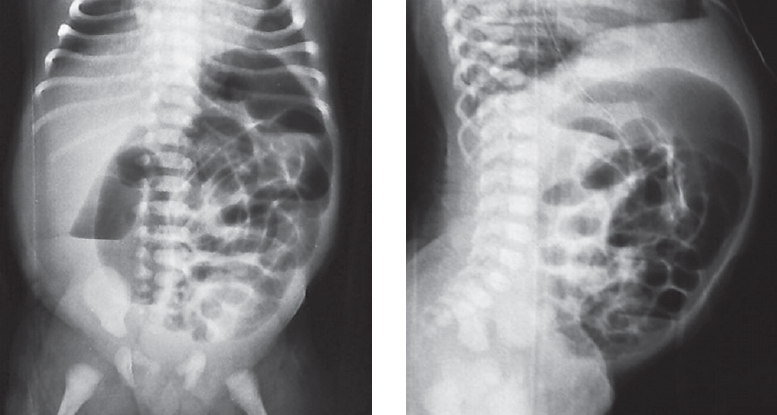

Болезнь Гиршпрунга, как правило, проявляется в первые дни жизни ребенка. Существование различных форм и вариантов ее проявления является основной причиной того, что у части пациентов заболевание не диагностируется в периоде новорожденности. C 2008 по 2019 г. в Детском городском многопрофильном клиническом специализированном центре высоких медицинских технологий г. Санкт-Петербурга находились на лечении 75 детей разного возраста с различными формами болезни Гиршпрунга. В 21 случае диагноз не был установлен сразу после рождения. У 11 новорожденных симптомы заболевания были неяркими и купировались сразу после опорожнения кишечника. У 2 детей с сопутствующей генетической патологией болезнь Гиршпрунга была заподозрена поздно, в связи с имеющимися особенностями опорожнения кишечника у этой группы больных. У части пациентов заболевание проявилось в виде стойкой задержки стула в более старшем возрасте. В статье приведены клинические примеры основных диагностических ошибок у пациентов с болезнью Гиршпрунга или подозрением на нее. Ошибки диагностики у детей раннего возраста связаны как с отсутствием хирургической настороженности у неонатологов родильных домов и отделений новорожденных, так и неправильной трактовкой клинической и рентгенологической картины. Дети в течение многих лет могут наблюдаться и лечиться у различных специалистов, прежде чем попадут в поле зрения детского хирурга.